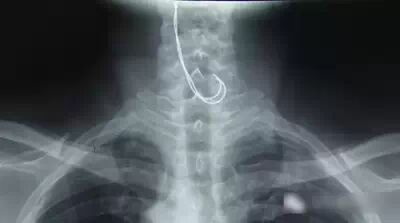

通過X光片,醫(yī)生看見病人的食道里有兩條底部帶彎鉤的強光陰影。據(jù)此判斷,病人吞下去的并不是一根筆直的鋼絲,而是折成兩段的。